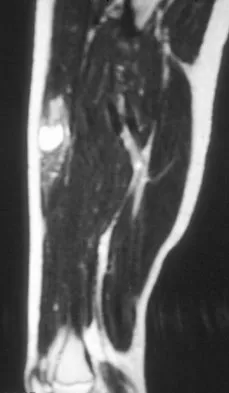

A 16-year-old boy has had thigh pain for the past several months. He denies any history of trauma. Examination reveals a large, deeply fixed, soft-tissue mass in the thigh. Laboratory results show an elevated erythrocyte sedimentation rate (ESR) and leukocytosis. A plain radiograph and MRI scan are shown in Figures 1a and 1b. Biopsy specimens are shown in Figures 1c and 1d. What is the most likely diagnosis?